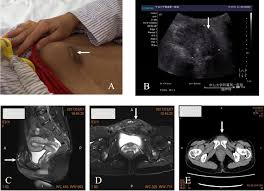

Below is a selection of pictures of endometriosis that have been taken during an operation. Small foci are seen here just under the serosa of the posterior uterus in the pouch of douglas. The gross appearance of endometriotic implants typically has been described as bluish gray, dark brown, or black powder burn lesions (fig. It is useful in comparing the gross appearance at the beginning of surgery and is somewhat predictive of surgical difficulty. Symptoms are absent in about half of women with ureteral disease, whereas 25% have flank pain and 15% gross hematuria. Endometrioid adenocarcinoma of the ovary. In response to hormonal shifts, these abnormal growths cause a great deal of pain and scarring within the abdominal cavity. Many patients with ute are asymptomatic until the disease is severe. Acog experts have been discussing how and for whom this treatment might be appropriate in women with endometriosis. These pictures will give you some idea of what endometriosis actually looks like. The purpose of this study is to evaluate the diagnosis of endometriosis by gross visualization and compare to histologic evaluation during laparoscopic resection. Griffith founded the lab in 2009 with the goal of helping researchers solve endometriosis, a chronic disorder in which tissue similar to that which normally lines the uterus instead grows. Endometriosis is found predominantly in women of childbearing age.

Endometriosis is a condition described as growth of ectopically located endometrial tissue in sites other than uterine cavity. The purpose of this study is to evaluate the diagnosis of endometriosis by gross visualization and compare to histologic evaluation during laparoscopic resection. Many patients with ute are asymptomatic until the disease is severe. What are the abnormality seen? Endometriosis the blood is darker and gives the small foci of endometriosis the gross appearance of powder burns.

Bloating is also associated with the condition, and while it causes. The purpose of this study is to evaluate the diagnosis of endometriosis by gross visualization and compare to histologic evaluation during laparoscopic resection. Endometriosis is a gynecological disease characterized by ectopic growth of endometrial glands and stroma outside the uterus. Usually surrounded by smooth muscle. The color is attributed to hemolyzed blood from ectopic endometrium that is encapsulated by adhesions or fibrotic tissue.